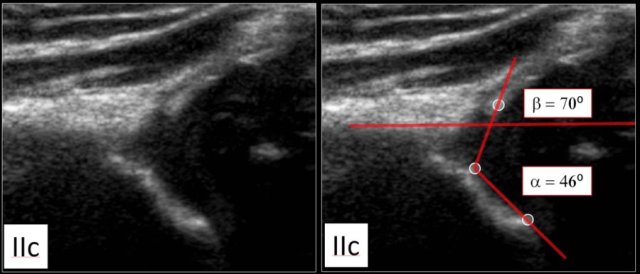

Type IIc

Here a type IIc hip.

The bony acetabular roof is severely deficient with a rounded to almost flat bony rim.

The alpha angle is 46 degrees.

The femoral head is still covered by the cartilaginous roof and the labrum.